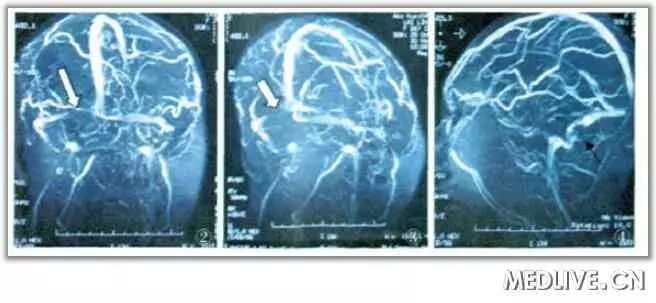

颅脑静脉核磁成像(MRV)示:双侧乙状窦、横窦血流信号断续(图2-4),周围可见多发迂曲小静脉影,下矢状窦明显变细小(图2),提示:颅内静脉窦及脑静脉血栓形成。

图2白色箭头示左侧横窦明显血流中断。图3白色箭头示左侧横窦明显血流中断。图4黑色箭头示右侧乙状窦起始处血流中断。